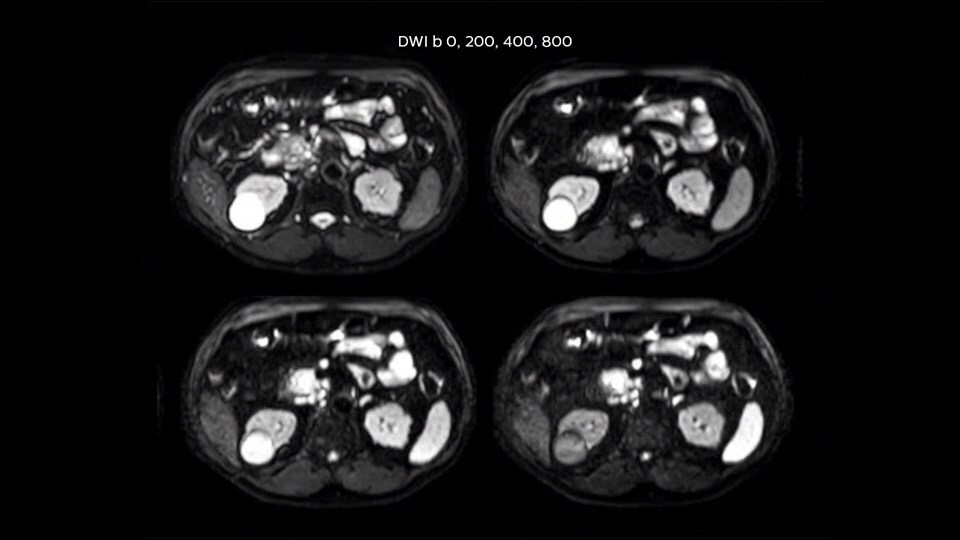

Clinical cases from nearly every anatomy

Explore 200+ clinical cases and download exam cards from peers around the globe, showcasing how Philips MR technology enhances your imaging capabilities.

Read more